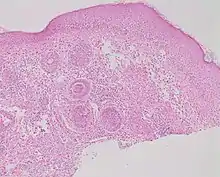

Studies of rosacea and Demodex mites have revealed that some people with rosacea have increased numbers of the mite,[12] especially those with steroid-induced rosacea. Demodex folliculitis (demodicidosis, also known as "mange" in animals) is a condition that may have a "rosacea-like" appearance.[15]

A 2007, National Rosacea Society-funded study demonstrated that Demodex folliculorum mites may be a cause or exacerbating factor in rosacea.[16] The researchers identified Bacillus oleronius as distinct bacterium associated with Demodex mites. When analyzing blood samples using a peripheral blood mononuclear cell proliferation assay, they discovered that B. oleronius stimulated an immune system response in 79 percent of 22 patients with subtype 2 (papulopustular) rosacea, compared with only 29% of 17 subjects without the disorder. They concluded, "The immune response results in inflammation, as evident in the papules (bumps) and pustules (pimples) of subtype 2 rosacea. This suggests that the B. oleronius bacteria found in the mites could be responsible for the inflammation associated with the condition."[16]